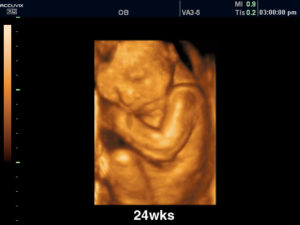

Атлас УЗИ — Плод, сердце, 24 недели, 3D (№315, Accuvix-XQ)

Протокол ультразвукового исследования сердца плода в режиме трехмерной визуализации.

Вашему вниманию предлагаются протокол трехмерного ультразвукового исследования сердца плода в режиме мультипланарной визуализации, алгоритм пошагового построения диагностических кардиальных сечений, включенных в расширенное эхокардиографическое исследование плода Трехмерное эхографическое исследование сердца плода, как и любое трехмерное исследование, начинается со сканирования сердца в режиме стандартного двухмерного ультразвукового изображения, необходимого для оптимизации ультразвукового изображения сердца плода, поиска оптимального эхо-доступа на уровне которого будет «взят» объем.